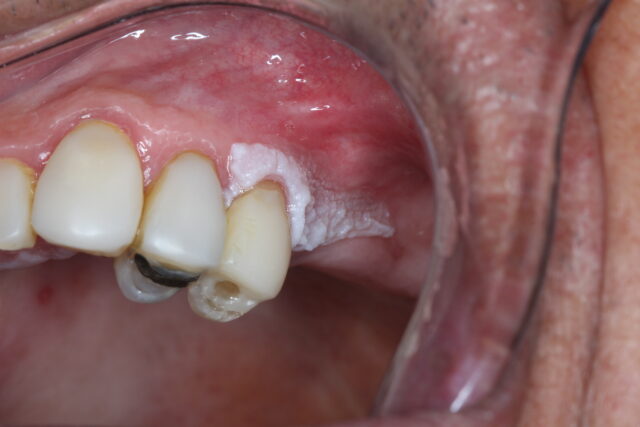

Leucoplasia é o nome dado a uma placa branca na mucosa da boca que não pode ser classificada como outra lesão conhecida.

Pode ser lisa, espessa, homogênea ou apresentar áreas irregulares.

A leucoplasia é considerada uma lesão potencialmente maligna, o que significa que algumas podem apresentar alterações celulares ao longo do tempo.